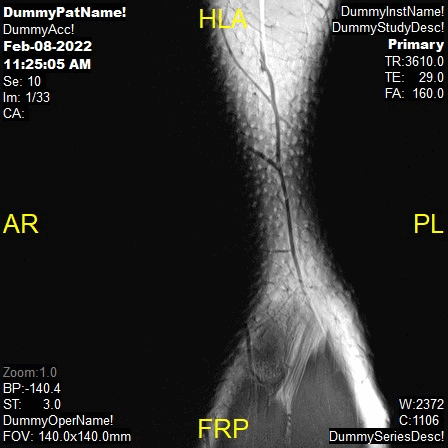

Planning

T2 Axial and PD FatSat Axial,

Parameters

Sample Image